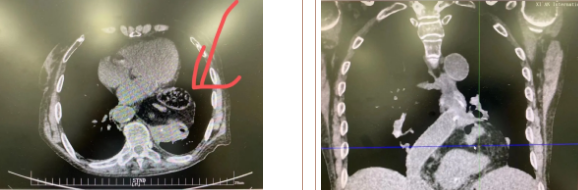

據(jù)了解,患者多年來進(jìn)食后出現(xiàn)惡心、嘔吐,卻未到醫(yī)院進(jìn)行檢查。3個月前患者突然出現(xiàn)無尿,全身腫脹等情況才前往就醫(yī),卻遭多家醫(yī)院拒收,輾轉(zhuǎn)來到我院就診。檢查發(fā)現(xiàn)患者已患宮頸癌、進(jìn)而引起腎后性腎衰、同時合并膈疝、出現(xiàn)泌尿道感染,病情及其復(fù)雜。

經(jīng)泌尿外科積極救治,患者腎衰癥狀緩解,隨后轉(zhuǎn)入放射治療中心進(jìn)行宮頸癌根治性放療。放療期間,患者惡心、嘔吐癥狀逐漸加重,后期無法進(jìn)食,排除機(jī)械性腸梗阻和放療因素,考慮因長期膈疝加重引起,經(jīng)胸外科會診后轉(zhuǎn)入胸外科一病區(qū)準(zhǔn)備手術(shù)治療。

麻醉手術(shù)中心副主任丁倩為減輕患者術(shù)后不適,實施單腔聯(lián)合支氣管封堵插管,同時進(jìn)行了肋間神經(jīng)阻滯麻醉。術(shù)中發(fā)現(xiàn)患者膈疝巨大,食管和疝囊分界不清,部分胃組織和結(jié)腸疝已進(jìn)入胸腔。李文海憑借豐富的臨床經(jīng)驗,仔細(xì)辨別解剖變異,有序完成分離、縫合、修補(bǔ)等一系列操作,胸外科穆強(qiáng)副主任醫(yī)師、劉歡住院醫(yī)師、麻醉手術(shù)中心團(tuán)隊通力配合,手術(shù)最終順利完成,患者安全返回胸外科監(jiān)護(hù)室病房。目前患者術(shù)后恢復(fù)良好,于近日準(zhǔn)備出院。